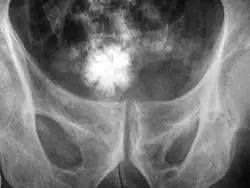

Large jackstone in the bladder of a 60-year-old man. Stone was removed by open cystolithotomy

A star-shaped Jackstone urolith can be seen in the urinary bladder on this radiograph of the pelvis

Jackstone calculi are rare bladder stones that have an appearance resembling toy jacks. They are almost always composed of calcium oxalate dihydrate and consist of a dense central core and radiating spicules. They are typically light brown with dark patches and are usually formed in the urinary bladder and rarely in the upper urinary tract. Their appearance on plain radiographs and computed tomography in human patients is usually easily recognizable. Jackstones often must be removed via cystolithotomy.[10]